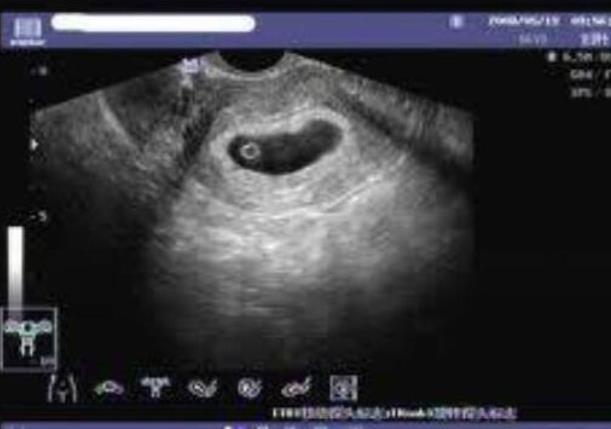

云南省试管婴儿医院选择较多,但无论是在云南九州医院还是云南省第一人民医院做试管,成功率都因人而异,大约在40%-50%左右。然而,在云南私立机构做试管时,必须查清楚医院的资质。近年来,许多正规生殖中心的辅助生殖周期数量逐年增加,保持了较高的成功率。以下依据15颗基础卵泡数量预测到云南私立医院做试管成功率,可参考下表: